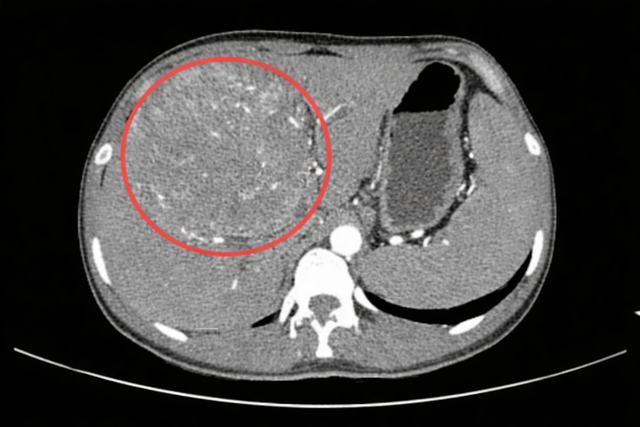

Mới đây, Bệnh viện Trung tâm Vịnh Binhai, thành phố Đông Quan, Trung Quốc đã tiếp nhận một ca bệnh khiến nhiều người không khỏi bàng hoàng. Bệnh nhân là một nam thanh niên 25 tuổi (tên đã được thay đổi), trên phim chụp cắt lớp vi tính (CT) xuất hiện dòng chữ lạnh lùng: “Khối u gan kích thước lớn”, kèm chẩn đoán ung thư gan giai đoạn cuối.

Ít ai ngờ rằng, cách đây 10 năm, khi còn là học sinh trung học cơ sở, chàng trai này từng được phát hiện dương tính với kháng nguyên bề mặt viêm gan B (HBsAg). Khi đó, vì còn trẻ, không thấy triệu chứng bất thường, anh chủ quan cho rằng “không sao”, không tái khám định kỳ, cũng không tham vấn bác sĩ chuyên khoa. Cho đến gần đây, khi tình trạng mệt mỏi kéo dài, bụng chướng ngày càng rõ, kết quả khám bệnh với chẩn đoán “ung thư gan giai đoạn cuối” mới thực sự giáng xuống như một cú sét giữa trời quang.